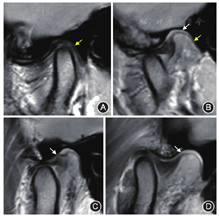

关节盘粘连是指张口时关节盘不能从关节窝向前移动到关节结节,而是仍保持在关节窝内(图4),典型关节盘粘连与关节运动受限相关[12]。

①正常双板区软组织张口位时为呈负压结构,此时软组织膨胀(上板与关节窝相接触,保持一致)改变[13],但发生损伤时负压消失,膨胀改变消失(图5);②斜矢状位PDWI可清晰显示上板区,为关节盘后上方一线样低信号结构,通常连续走行,信号连续性中断提示上板撕裂改变(图5C)。